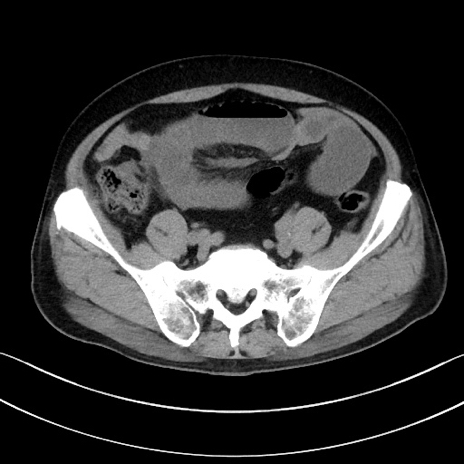

症例15(横断像)

【症例】70歳代男性

【主訴】腹痛

【現病歴】今朝から腹痛あり。全体的に痛い。特に左上の方。排ガスが今日はない。冷や汗が出る。

【既往歴】直腸癌術後

【身体所見】左側腹部〜上腹部に圧痛あり。腹膜刺激症状明らかなではない。軽度反跳痛。左下腹部に術後瘢痕あり。

【データ】WBC 7700、CRP 0.02